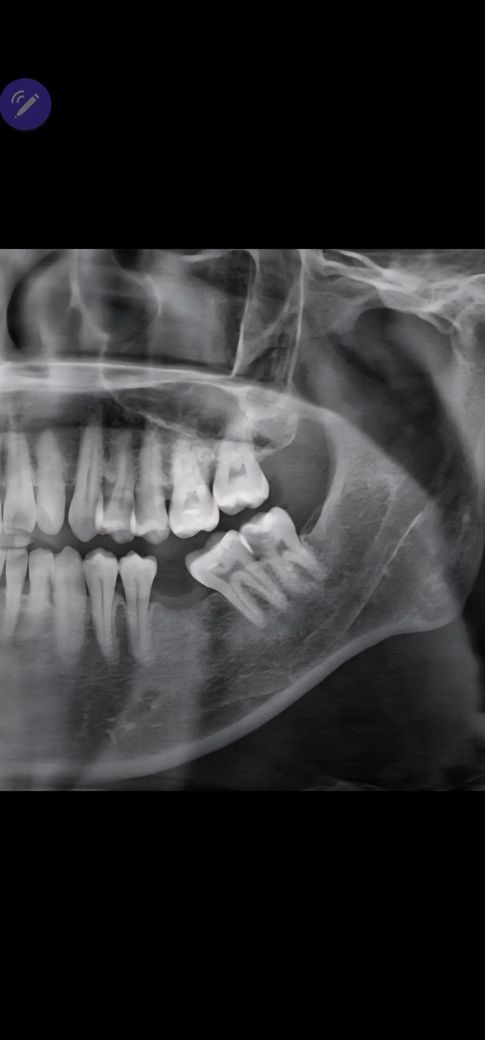

사랑니 상태 어떤지 봐주세요 뽑기 어려울까요?

사랑니 통증이 있어 뽑으려는데 통증 있는 상태에서는 뽑기어렵다하여 5일치 항생제와 소염진통제를 처방받아 먹고 있는 상황인데 광대와 귀까지도 통증이 간혈적으로 있고 밥도 먹기 힘든 상태에 치통때문인지 감기가 올듯말듯한 코 목 통증까지 있어 빨리 뽑고 싶습니다

엑스레이는 현상태는 아니고 앞전에 찍어둔거긴한데 상태가 어떤지 봐주세요(경사매복, 신경근접, 뿌리 염증 상태 등등 궁금합니다)

난이도가 높아보이진 않습니다 바르게 나 있고 신경관이랑 거리도 있고요

다만 염증상태라 마취가 잘 안될 수 있어 약 먼저 복용하여 급성 염증 가라앉히라는겁니다